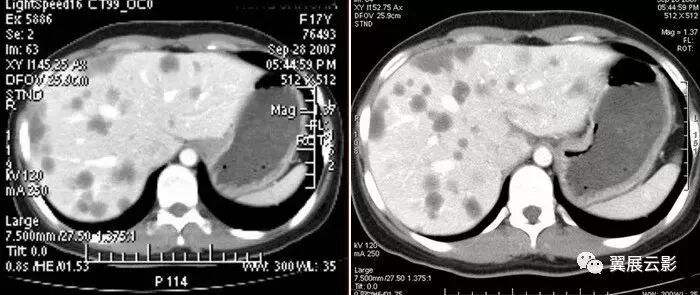

(该图来自《CT泪滴状肠系膜上静脉征评价胰头癌不可切除性的意义》一文, 中国医学影像技术2001年第17卷第2期)

图1 动态增强CT 示胰头部肿块紧邻 SMV、SMA,周围正常脂肪间隙消失,SMV受压呈泪滴状。

图2 螺旋增强CT 示胰钩突部一低密度肿块,SMA包绕受侵,SMV受压呈线形改变

图3 动态增强CT 示胰头部一密度不均匀肿块,与 SMV脂肪间隙消失,SMV受压呈椭圆形改变。

图4 螺旋增强CT 示胰头部一密度不均匀肿块,与 SMV脂肪间隙模糊但仍存在,三角形的 SMV为容积效应所致。